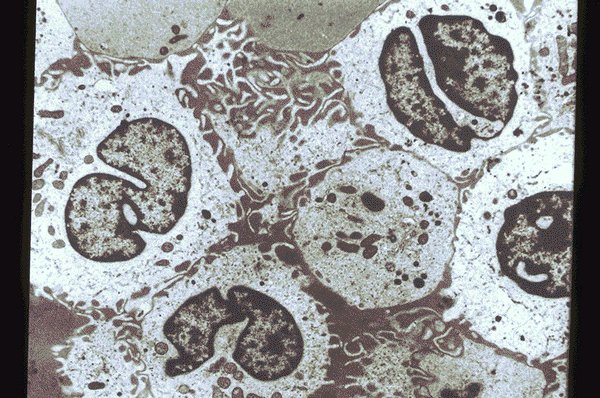

Set 2 Normal and Abnormal Bone Marrow Aspirates

Slide 200 of 260 Image ID 3653

Hairy cell leukemia. Electron photomicrograph.

Electomicrograph of a specimen of blood from a

patient with Hairy cell leukemia. The Hairy cells in

this specimen is characterized by numerous

delicate cytoplasmic pseudopods and lobulated

and folded nuclei which have relatively finely

dispersed chromatin.